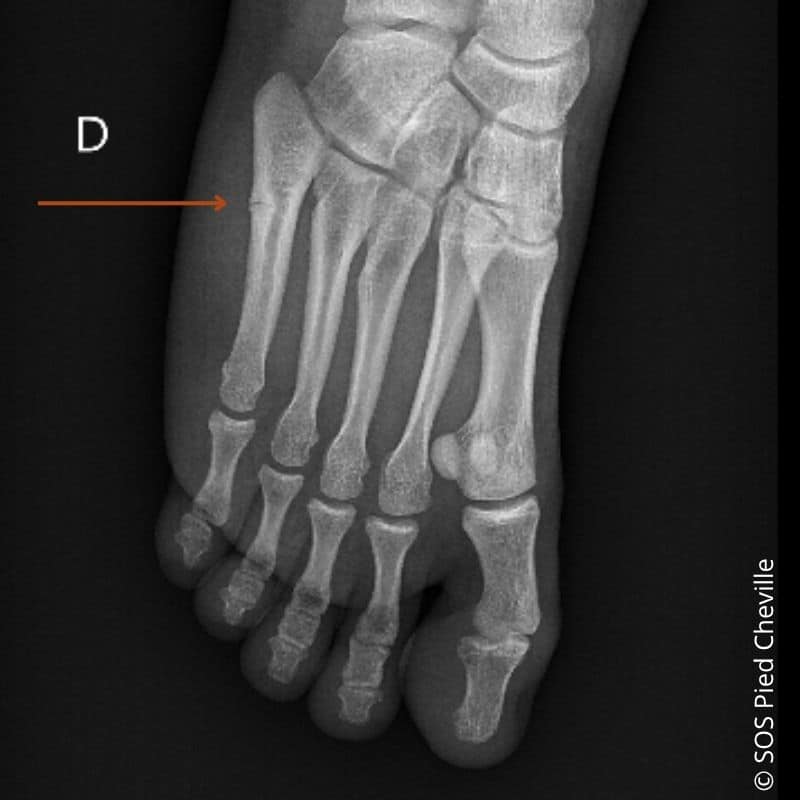

Fracture de Jones ou fracture de la base du 5ème métatarsien

La fracture de Jones correspond à une fracture de la base du 5ème métatarsien, entre l’articulation et la diaphyse du 5ème métatarsien.

RADIO : PIED FACE PROFIL EN CHARGE et OBLIQUE